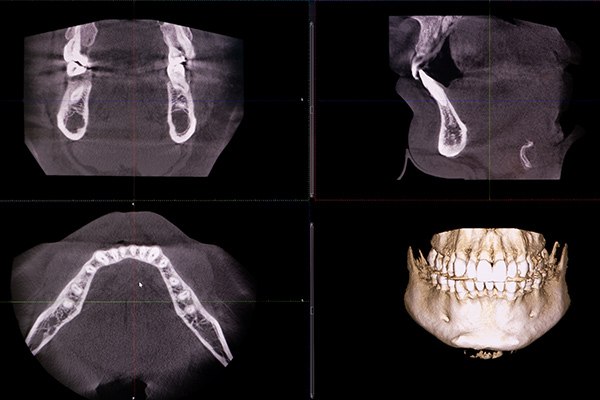

平面的なレントゲンでは見えない、顎の骨や神経の走行などを3次元で正確に観察し、より安全で確実な診断と治療計画の立案を可能にします。